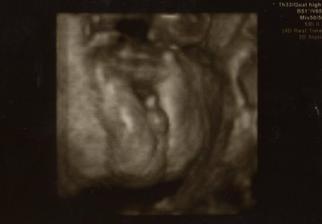

2.3.2010, 22+4tt - 3D UTZ